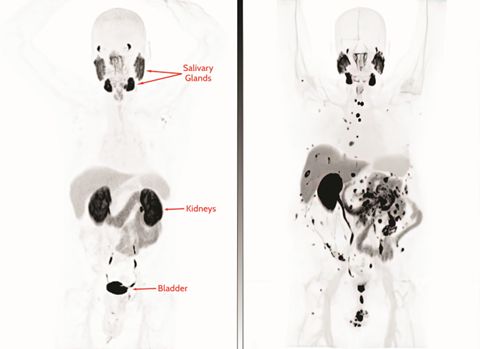

Left panel: A patient’s PSMA PET scan shows no metastases.

Right panel: A patient’s PSMA PET scan shows extensive metastases to the bones, lymph nodes, and lining of the abdomen (peritoneum).

Note that uptake to the salivary glands is normal, since PSMA is expressed there. Also note that the contrast is emptied through the kidneys and bladder, and this is also normal. See arrows in image at left.